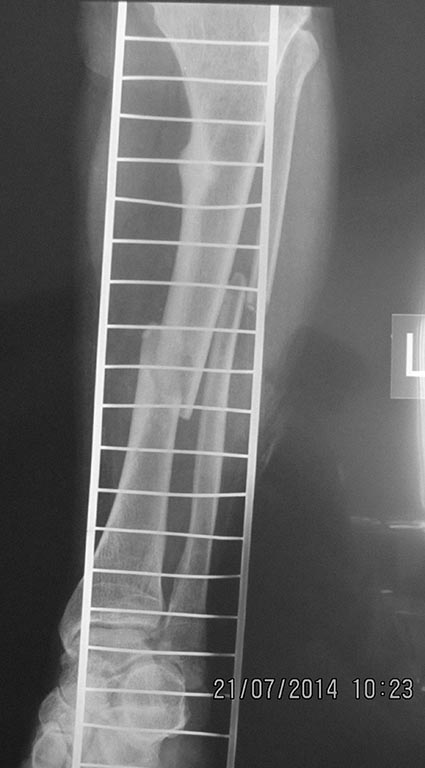

[Ortho] перелом бедра с исходной деформацией

Имя     : IMG_2892.jpg

Тип     : image/jpeg

Размер  : 54362 байтов

Url     : http://weborto.net:8080/pipermail/ortho/attachments/20140721/a09be377/attachment-0009.jpg